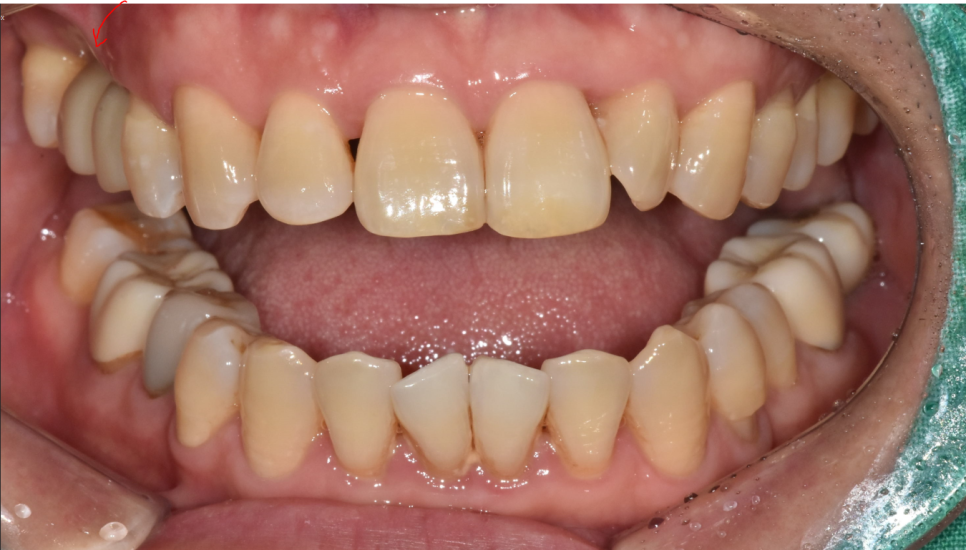

240102

빨간색 화살표가 임플란트 보철입니다.

너무나 자연스럽죠~?

환자분들께서는 임플란트 해 넣은 치아인지

전혀 모르실꺼같아

표시 한번 해보았습니다.

9개월이라는 대장정이었습니다.